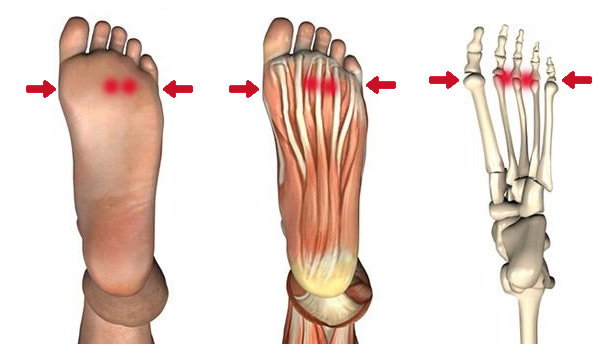

L’hallux valgus est une déformation du gros orteil qui se caractérise par un écartement anormal de celui-ci vers les autres orteils, souvent accompagné d’une saillie osseuse à la base du gros orteil. En podologie, la prise en charge de l’hallux valgus vise généralement à soulager la douleur, à améliorer la fonctionnalité du pied et à prévenir la progression de la déformation.